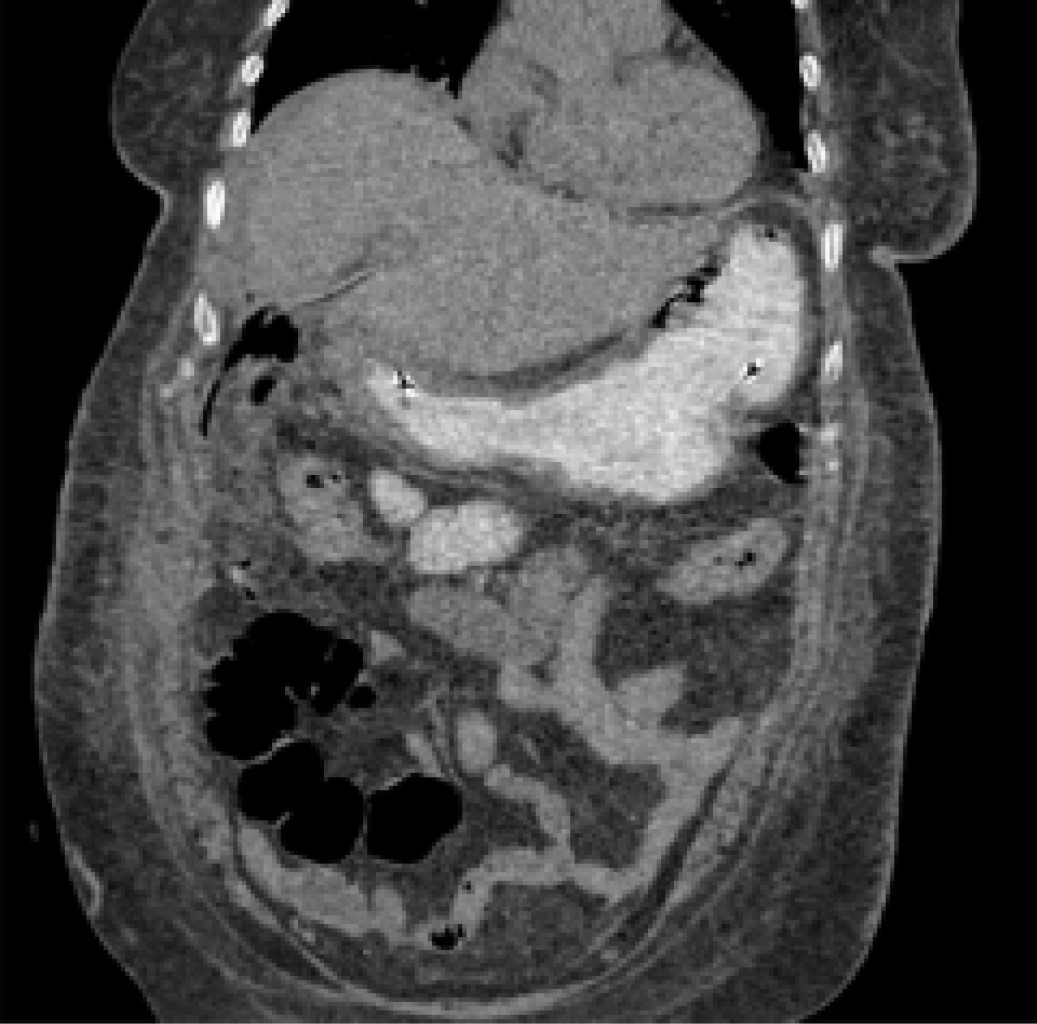

The patient was a 59-year-old female with a history of type 2 diabetes mellitus of long evolution. She came to the emergency department with colicky pain in the right hypochondrium after six months of evolution, intensity 6/10 on the visual analog scale, without irradiation, associated with the ingestion of cholecystokinetic foods, without mitigating factors. She denied fever, jaundice, choluria, or acholia. On physical examination, the Murphy sign was absent, with pain on deep palpation in the right hypochondrium, with no evidence of peritoneal irritation. She has the following laboratories: hemoglobin 12.9 g/dl, hematocrit 37%, leukocytes 9.4 × 103/µl, platelets 360 × 103/µl, glucose 178 mg/dl, creatinine 0.7 mg/dl, sodium 145 mEq/l, potassium 3.7 mEq/l, chlorine 105 mEq/l, total bilirubin 0.7 mg/dl, alkaline phosphatase 55 U/l. Ultrasound of the liver and biliary tract was performed, which revealed an increased echogenicity of the gallbladder throughout its extension, causing a wall-echo-shadow (WES) phenomenon and measuring 52.7 × 29.4 × 18.7 mm. The wall was non-evaluable; the common bile duct measured 5.8 mm, with no evidence of any litho inside (Figure 1). An abdominal tomographic scan showed a heterogeneous gallbladder with a volume of 13.2 cm3, with the presence of air density and a regular thickened wall with the presence of calcifications, a distended stomach, and the presence of a hyperdense image inside resembling a probable litho (Figure 2).

Figure 2